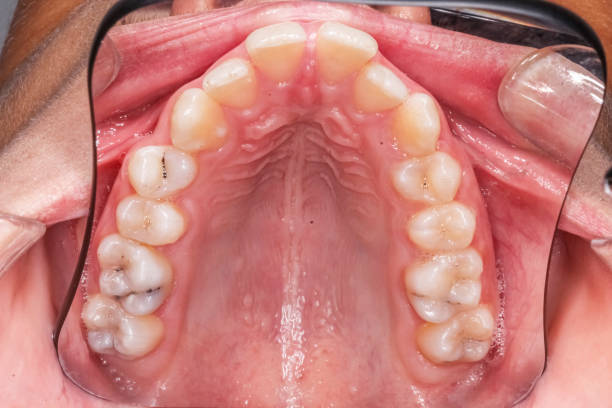

¿Qué es el stripping dental o IPR?

El stripping dental, también conocido como IPR (Interproximal Reduction) o reducción interproximal del esmalte, es un procedimiento mediante el cual el ortodoncista lima una pequeña cantidad de esmalte en las caras laterales de los dientes para crear espacio entre ellos. La reducción es mínima —entre 0,2 y 0,5 milímetros por punto de contacto— y se realiza de forma controlada con instrumentos de precisión calibrados en fracciones de milímetro.

El objetivo principal es ganar espacio en la arcada dental sin recurrir a extracciones. Al reducir ligeramente el ancho de uno o varios dientes, el ortodoncista puede moverlos a su posición correcta sin comprometer la estructura interna. El esmalte dental no contiene nervios, por lo que el procedimiento no produce dolor.

Corregir la discrepancia de Bolton. Este índice mide la proporción entre el tamaño de los dientes superiores e inferiores. Cuando existe desproporción, el stripping permite reequilibrar el tamaño de ciertas piezas para que la mordida cierre correctamente.

Eliminar los triángulos negros. Estos espacios oscuros entre dientes de forma triangular se reducen recontorneando la zona de contacto interproximal.